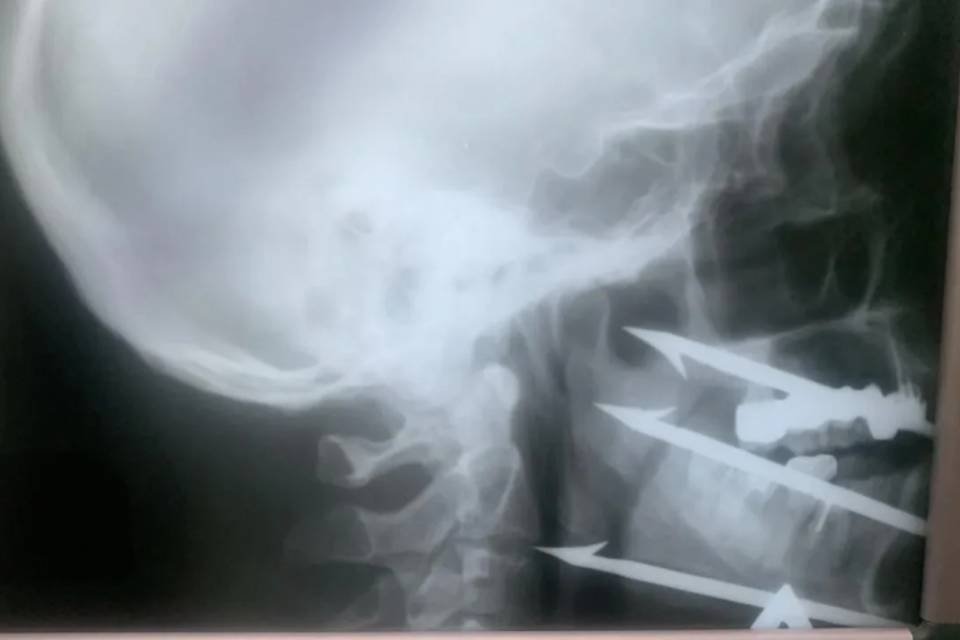

52-летнего мужчину доставили в Волгоградскую городскую клиническую больницу №1 с тяжелым ранением, полученным во время подводной охоты. Он случайно выстрелил себе в лицо трехзубым гарпуном, который там и застрял, почти задев сонную артерию. Это создало опасную ситуацию, так как любое неосторожное движение могло привести к трагедии. Врачи быстро собрали команду для операции. Врач челюстно-лицевого отделения больницы №1 Роман Стасюк, признанный лучшим хирургом региона в 2025 году, и сосудистый хирург больницы №25 Олег Виноградов успешно извлекли гарпун, сохранив важные сосуды и нервы. Сейчас жизнь пациента вне опасности, и ему предстоит реабилитация.